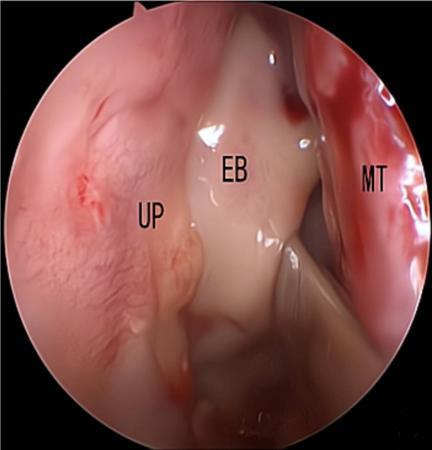

摘要:目的 探究经中鼻甲基板入路的手术技巧及临床效果,旨在系统评估一种兼具良好手术视野和微创性的蝶窦开放径路。方法 回顾性分析2019年9月-2023年9月该院收治的35例孤立性蝶窦病变或单侧蝶窦伴毗邻筛窦受累患者的临床资料,均经中鼻甲基板入路的“四步”程序化操作开放蝶窦。观察手术相关情况和并发症发生情况;采用视觉模拟评分法(VAS)评分,评估头痛和流涕等症状改善情况;采用改良隆德-肯尼迪(MLK)评分,评价术腔恢复状况。结果 所有患者术中保留钩突、中鼻甲和筛泡,26例(74.3%)保留上鼻甲;所有患者均达到临床治愈标准,表现为:术腔引流通畅,黏膜完全上皮化,以及蝶窦开口维持良好开放状态。术后病理显示:蝶窦霉菌病19例(54.3%),蝶窦息肉7例(20.0%),蝶窦黏膜慢性炎症9例(25.7%)。所有患者均未发生严重并发症,仅1例(2.9%)于术后12 d出现中鼻甲创面渗血,经电凝止血后治愈。头痛VAS评分由术前的(4.71±1.66)分,降至术后的(0.83±0.39)分,手术前后比较,差异有统计学意义(t = 13.71,P < 0.01);流涕VAS评分由术前的4.00(0.00,6.00)分,降至术后的0.00(0.00,1.00)分,手术前后比较,差异有统计学意义(Z = -4.47,P < 0.01);手术前后嗅觉减退VAS评分比较,差异无统计学意义(P > 0.05)。MLK评分由术前的4.50(2.00,4.00)分降至1.00(0.00,1.00)分,手术前后比较,差异有统计学意义(Z = -5.20,P < 0.01)。结论 经中鼻甲基板入路蝶窦开放术,严格遵循鼻窦解剖层次,在最大限度地保留鼻腔生理结构的前提下,可获得理想的术野暴露。该术式对于局限于蝶窦及后组筛窦的病变,具有确切的临床疗效。值得应用于临床。